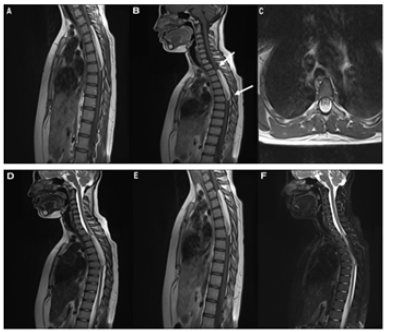

We present a case of a 17-year-old female, previously healthy who is admitted with a history of lower limb weakness of 1 year of evolution that blocks gait and bladder dysfunction characterized by urinary incontinence. Neurological examination showed 1/5 lower limb weakness, hyperreflexia, hypoesthesia from the T8 medullary level, sign of Babinski. MRI showed an elongated and ovoid intramedullary lesion with evident medullary widening from T3 to T7. The intramedullary lesion arose from the posterior aspect of the thoracic spinal cord. On T1- weighted images the lesion was hyperintense and on fast spin echo T2-weighted images the lesion was partially hyperintense. With the gadolinium administration, the lesion showed intense enhancement. On short tau inversion recovery sequence images, the lesion appeared profoundly hypointense Figure 1. We performed a microsurgical resection of the lesion. The patient was placed in the ventral position. We used electromyography and evoked potentials during the procedure. We performed laminectomy from T3 to T7 to expose the poles of the lesion and performed a longitudinal durotomy on the midline. Under microscopic vision, a myelotomy was performed on the midline and we used CUSA to perform a devastation of the lesion until to reach the limits of the anterior cords; simultaneously using bipolar coagulation and micro scissors. Once considerable devastation had been performed, the portion adhered to the anterior spinal cords was partially resected, avoiding direct bipolar coagulation. Finally, a partial resection of the tumor of approximately 70% was achieved. Surgical hemostasis was carefully verified. A Dural closure was completed leaving a wide spinal canal. We perform laminoplasties of the operated levels Figure 2. During the immediate postoperative period, there were no clinical changes, however, after the first month, the patient presented improvement in the strength of both legs, achieving assistance walking. At the 6-month follow-up, the patient showed walking without support and urinary sphincter control. Histopathological analysis reported a lesion compatible with lipoma Figure 3. MRI at 1 year follow up showed residual lesion Figure 4.

Figure 1: (A)(B) Sagittal (C) Axial T1 weighted image. There is a hyperintense intramedullary ovoid and fusiform lesion. The lesion spans along five vertebral bodies at level of T3-T7 (arrows). (D) Sagittal T2 weighted image. The lesion demonstrates high signal intensity, consistent with fat component. (E) Sagittal post Gad T1 weighted image. There is a moderate enhancement of the lesion. (F) Sagittal STIR. The lesion exhibit very low signal (hypointense), confirming fat content.